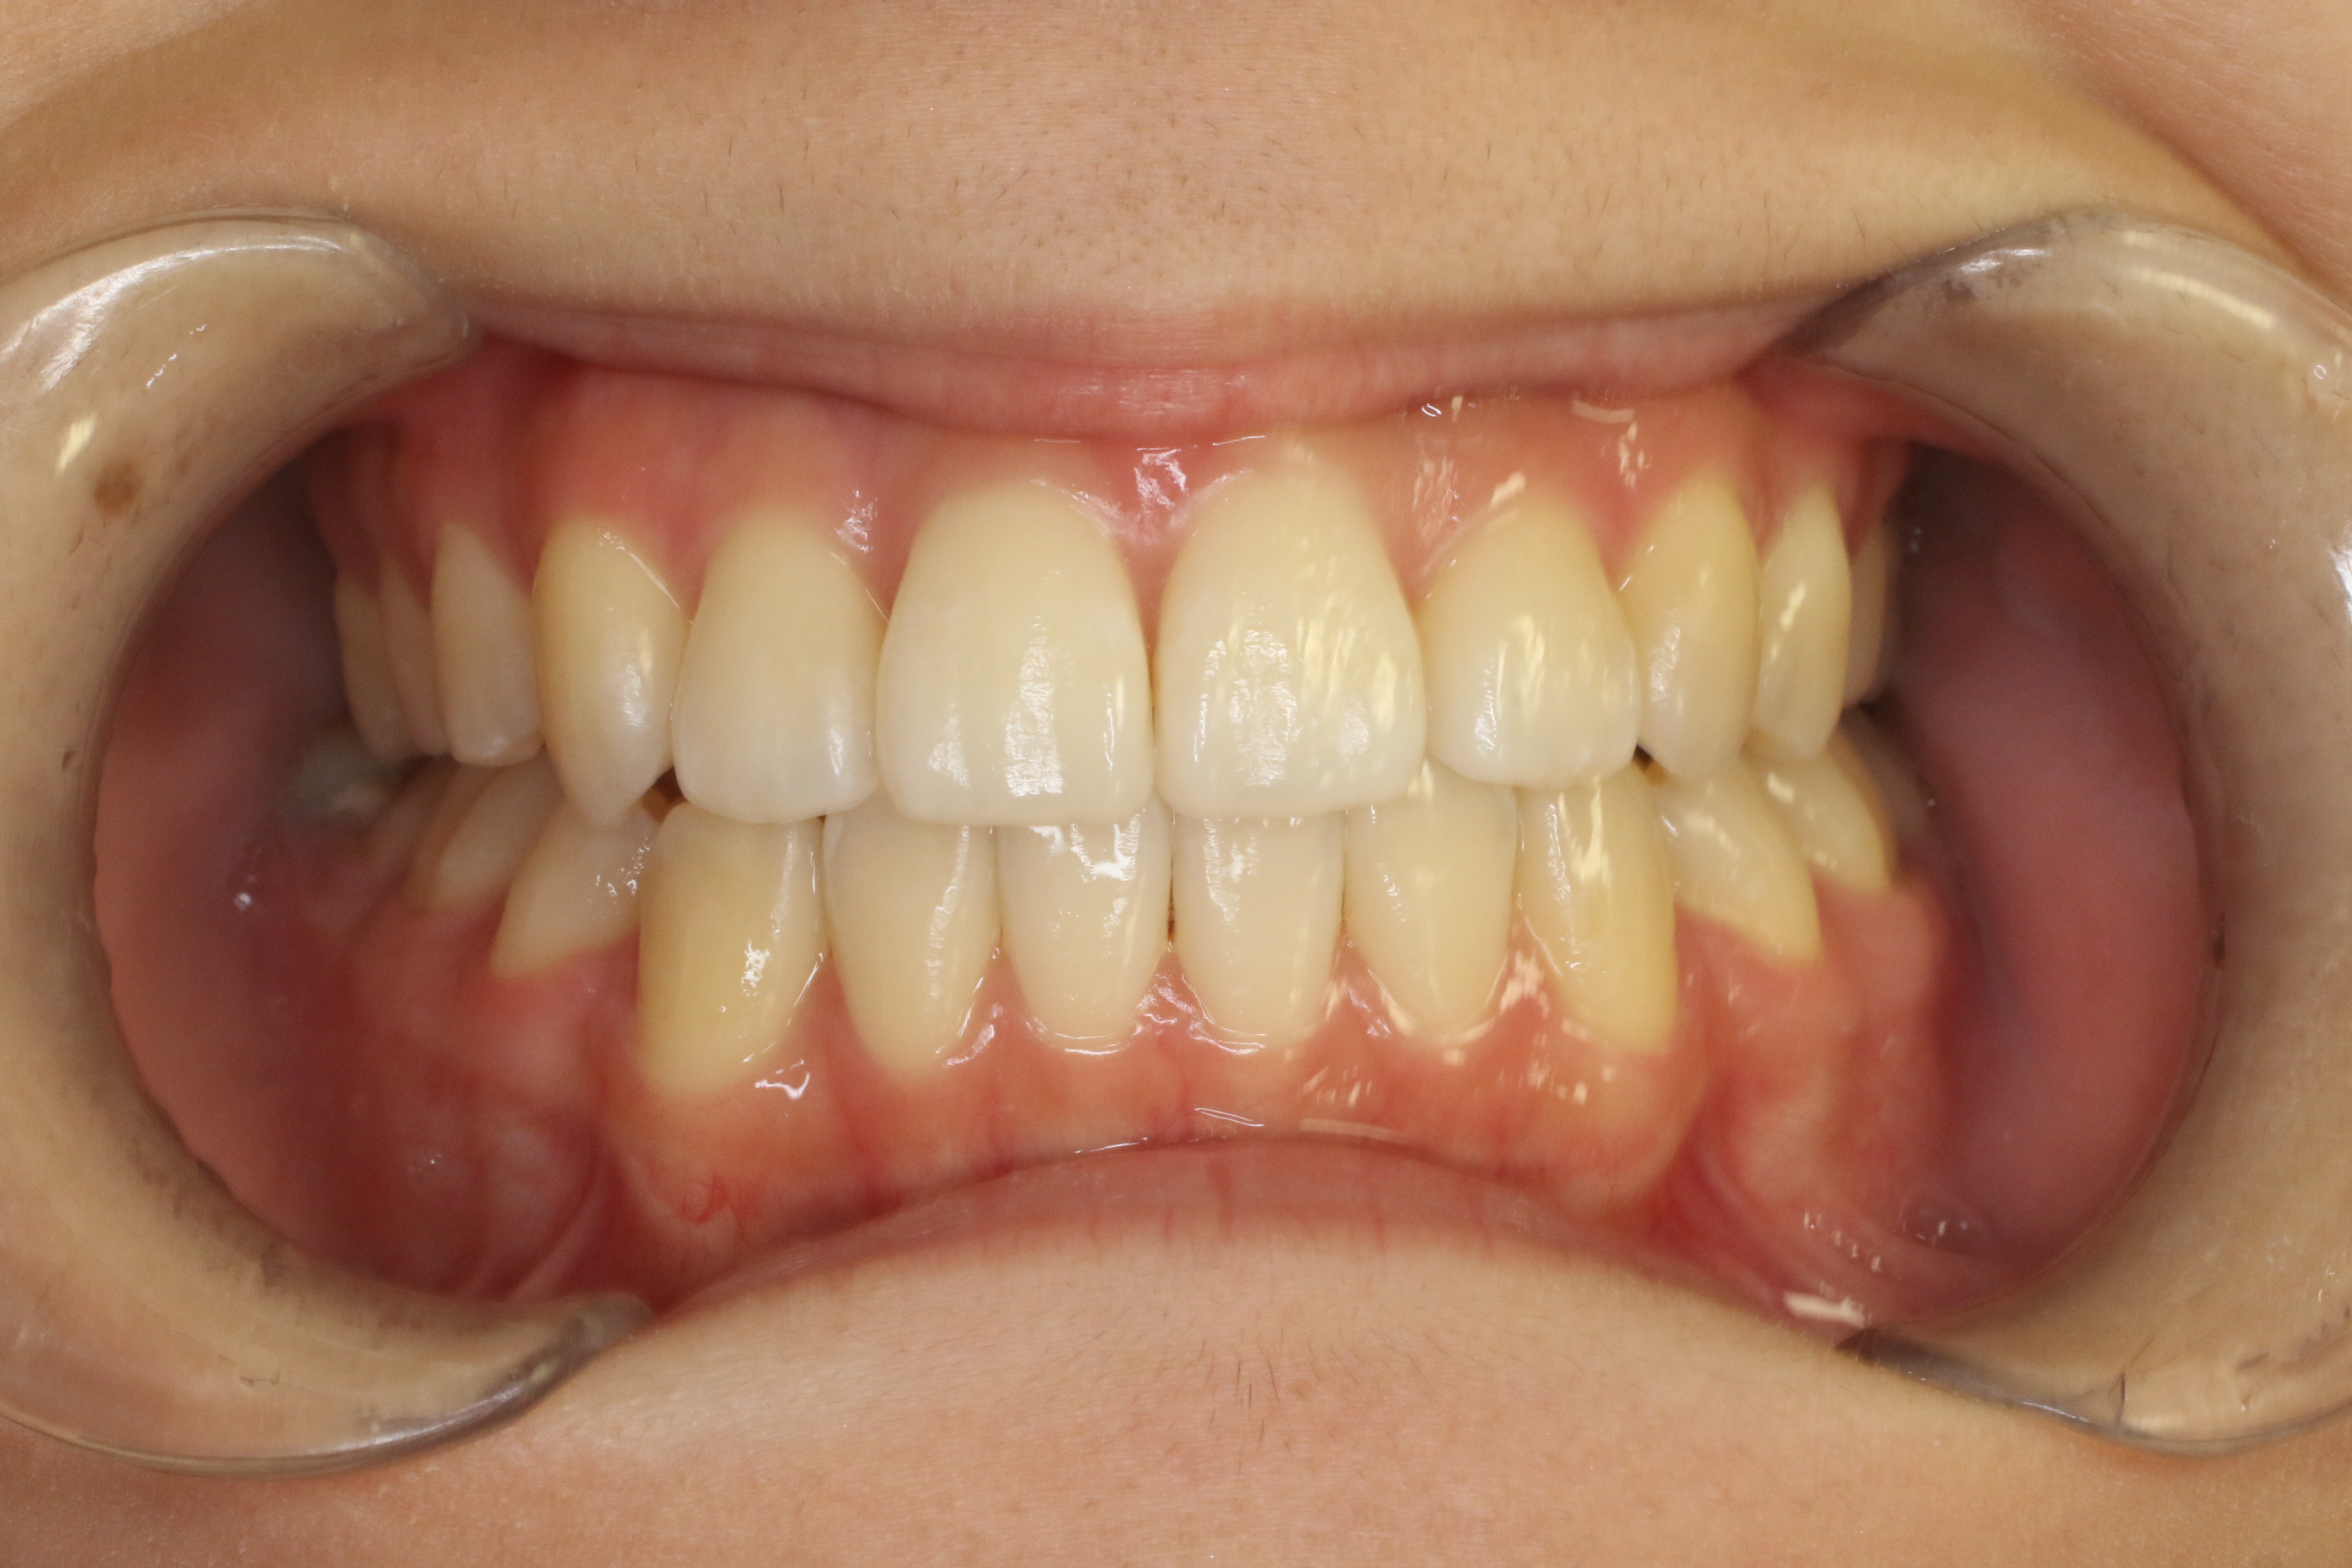

すきっ歯を治したい

年齢層 20代

性別 女性

主訴 【主訴】すきっ歯を治したい 【診断・症状】空隙歯列、1,1正中離開

治療費用 検査・診断:38,500-/裏側矯正治療:1,397,000-(※全て税込)

治療期間 約1年8か月(22回)

抜歯 無(非抜歯)

矯正の装置 裏側矯正(舌側矯正)

副作用、リスク 歯肉退縮,歯根吸収,疼痛,咬合の違和感,装置の違和感,虫歯,歯肉炎